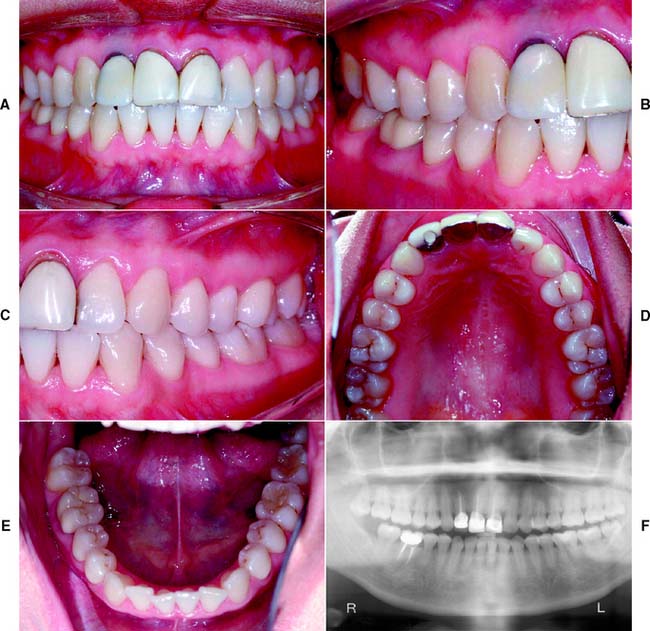

This class (Figs. 1-27 and 1-28) is characterized by ideal or minimal compromise in the location and extent of edentulous area (which is confined to a single arch), abutment conditions, occlusal characteristics, and residual ridge conditions. All four of the diagnostic criteria are favorable.

Fig. 1-27 Class I patient. This patient is categorized as Class I because of an ideal or minimally compromised edentulous area, abutment condition, and occlusion. There is a single edentulous area in one sextant. The residual ridge is considered type A. A, Frontal view, maximum intercuspation. B, Right lateral view, maximum intercuspation. C, Left lateral view, maximum intercuspation. D, Occlusal view, maxillary arch. E, Occlusal view, mandibular arch. F, Frontal view, protrusive relationship. G, Right lateral view, right working movements. H, Left lateral view, working movement. I, Full-mouth radiographic series.

(From McGarry TJ, et al: Classification system for partial edentulism. J Prosthodont 11:181, 2002.)

Fig. 1-28 Class I patient. The patient is categorized as Class I because an ideal or minimally compromising tooth condition, and occlusal scheme is exhibited. A single large amalgam core restoration requires a complete coverage restoration in one sextant. A, Frontal view, maximum intercuspation. B, Right lateral view, maximum intercuspation. C, Left lateral view, maximum intercuspation. D, Occlusal view, maxillary arch. E, Occlusal view, mandibular arch. F, Panoramic radiograph.

(From McGarry TJ, et al: Classification system for the completely dentate patient. J Prosthodont 13:73, 2004.)